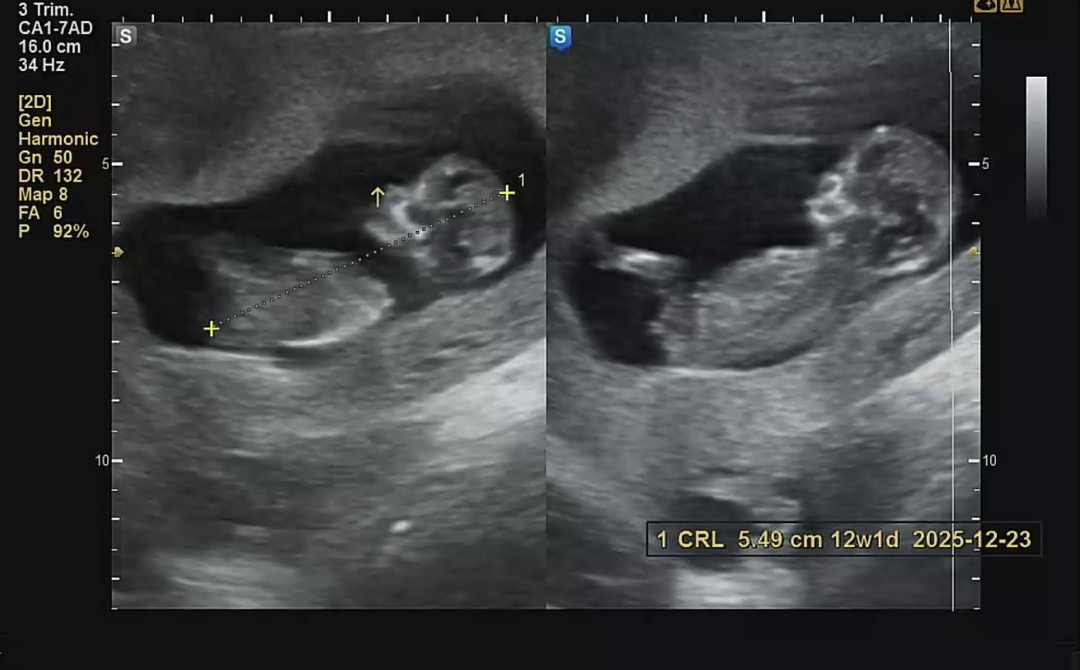

임신이처음이라 모든게 낯설고 신기하네요..ㅎㅎ 오늘12주여서 초음파보고왔는데 각도법이런걸볼줄몰라서.. 봐주실수있나요??

오른쪽 사진으로 봤을때 돌기 각도가 솟구쳐서 아들 각도처럼 보입니다